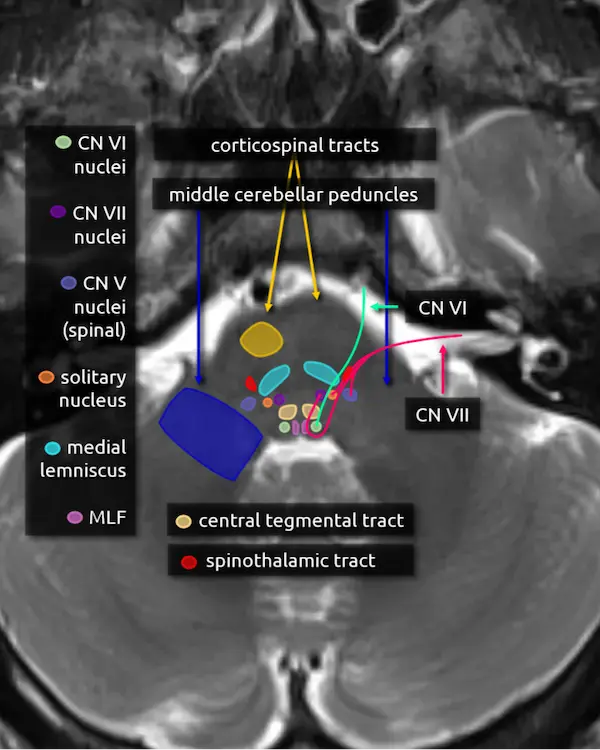

1. Corticospinal tracts

2. Middle cerebellar peduncles

3. Medial lemniscus

4. Medial longitudinal fasciculus (MLF)

5. Abducens nucleus (CN VI)

The abducens nucleus is located in the dorsal pons at the level of the internal auditory canals. The facial colliculi are the two bumps along the dorsal surface of the pons at this level, which are formed by the facial nerve coursing over the abducens nucleus.

Absence of the abducens nucleus occurs in horizontal gaze palsy with progressive scoliosis (HGPPS), which results in an abnormal contour of the posterior pons due to flattening of the facial colliculi.

6. Abducens nerve (CN VI)

The abducens nerve courses anteriorly from the abducens nucleus and exits the ventral pons at the pontomedullary junction. After traversing the prepontine cistern, the nerve enters Dorello's canal, where it is relatively fixed in place. It also has the longest subarachnoid course of the cranial nerves. These two features make it particularly susceptible to stretching-related injury, e.g., in the setting of brain herniation. After Dorello's canal, the nerve enters the cavernous sinus, where it is susceptible to mass effect from space occupying lesions, e.g., a mass or a cavernous internal carotid artery aneurysm.

The abducens nerve innervates the ipsilateral lateral rectus muscle, responsible for eye abduction. Damage will cause horizontal diplopia.

7. Facial nucleus (CN VII)

The facial nucleus is located in dorsal pons anterior to the abducens nucleus and posterior to the medial lemniscus.

8. Solitary nucleus

The solitary nucleus is located lateral to the facial nucleus in the lower pons and extends to the upper medulla. It contributes to the facial, glossopharyngeal, and vagus nerves.

Damage to the solitary nucleus may manifest as decreased taste sensation on the ipsilateral tongue.

9. Spinal nucleus of the trigeminal nerve (CN V)

The spinal nucleus of the trigeminal nerve is the inferior continuation of the main sensory nucleus of the trigeminal nerve (see level 3). It is involved in sensation of the head and face. It receives afferent fibers from the facial, glossopharyngeal, and vagus nerves.

10. Facial nerve (CN VII)

The facial nerve courses posteriorly from the facial nucleus before looping over the ipsilateral abducens nucleus and exiting the anterolateral pons at the pontomedullary junction. It then enters the internal auditory canal with the vestibulocochlear nerve (CN VIII). Four nuclei contribute to the facial nerve; the three listed above, and a fourth called the superior salivary nucleus responsible for parasympathetic fibers located medial to the facial nucleus, not pictured here. The nerve has motor, sensory, and parasympathetic functions:

Motor:

a. Face (muscles of expression)

b. Stylohyoid, stapedius, posterior belly of the digastric muscle

Sensory:

a. Taste (anterior 2/3 of tongue, floor of mouth, palate)

b. Somatic sensation (posterior EAC, mastoid, lateral pinna)

Parasympathetic:

a. Salivary glands (submandibular sublingual)

Similar to the trigeminal nerve, the facial nerve may become irritated by nearby blood vessels (neurovascular compression syndrome), manifesting as hemifacial spasm.